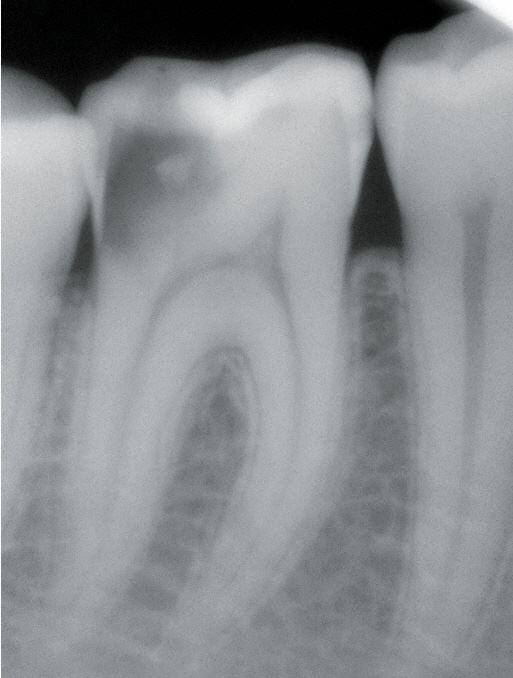

Röntgendiagnostik

Aus heutiger Sicht geht es nicht nur um die Entscheidung, ob ein bestimmter Zahn oder eine bestimmte Zahnfläche eine Restauration benötigt, sondern es geht auch darum, durch die Kariesdiagnostik Phasen aktuell hoher oder niedriger Kariesaktivität zu erkennen.

Unterschieden werden initiale Karies, Dentinkaries sowie Fissurenkaries, Approximalkaries und Wurzelkaries.

Die klinische Untersuchung, insbesondere die visuelle Inspektion (Lupenbrille) sind Standard, um auch die "hidden caries zu erkennen. Zusätzliche Maßnahmen können Röntgenaufnahmen und Kariesdetektoren sein, um Frühstadien zu erkennen.